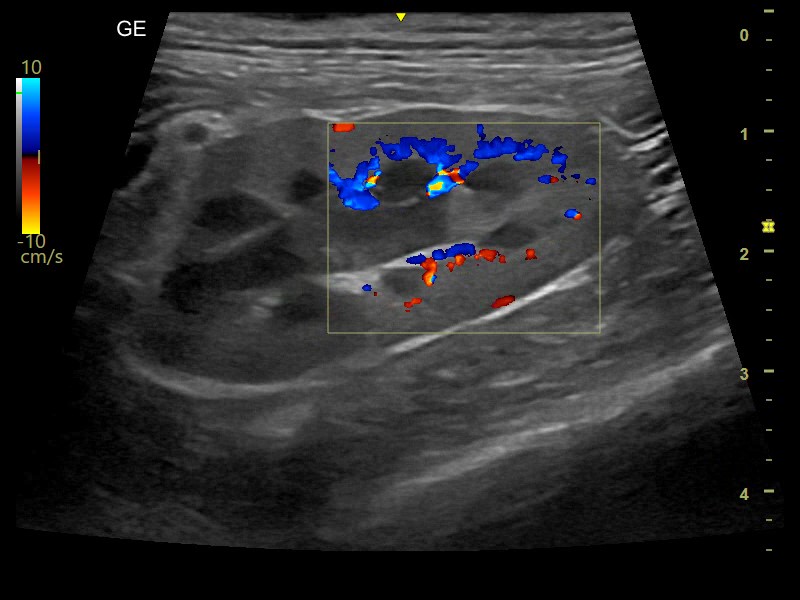

Tecnologia di imaging di elevata qualità

Versana Premier™ è una soluzione completa che aiuta ad implementare le prestazioni veterinarie, bilanciando alla perfezione convenienza ed efficacia. Offre una potenza di imaging ai più alti standard mondiali e un'estrema chiarezza per aumentare l'affidabilità diagnostica.

Versana Premier ™ offre potenza e chiarezza di imaging straordinarie per una maggior sicurezza diagnostica. Consente di avere un'ottima qualità dell'immagine, differenziare i tessuti e delineare le interfacce delle strutture.

- B-Flow™ e Color B-Flow™